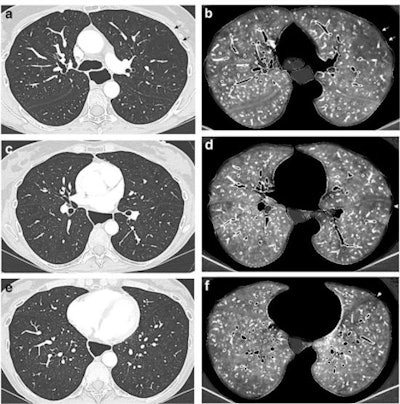

DECT angiographic exam obtained in a 55-year-old female nonsmoker with limited cutaneous systemic sclerosis diagnosed 24 years earlier (170 cm, 50 kg). Stable diffusing capacity of the lung alteration over two years. Paired lung and perfusion images obtained at the level of the upper (a, b), mid (c, d), and lower (e, f) lung zones. Absence of CT features of interstitial lung disease on lung images (a, c, e). Bilateral perfusion defects, combining patchy defects in both lungs (b, d, f), marked subpleural hypoperfusion in the lingula and left lower lobe (arrowhead; d, f) and a large triangular, pulmonary embolism-type perfusion defect (arrows; b) in the left upper lobe with reduced number of vascular sections in the corresponding lung image (arrows, a). No morphologic CT features of acute and/or chronic pulmonary embolism. Note the presence of marked esophageal dilatation. (All figures courtesy of Antoine Dupont, Prof. Martine Remy-Jardin and European Radiology).Systemic sclerosis is an autoimmune connective tissue disorder that is characterized by a complex interplay of vascular abnormalities, immune system activation, and an uncontrolled fibrotic response. While the organ most commonly affected is the skin, systemic sclerosis is a systemic disease with the potential for multiple organ system involvement with special mention of the lungs and pulmonary vessels, recognized as a major cause of morbidity and mortality, the researchers wrote.